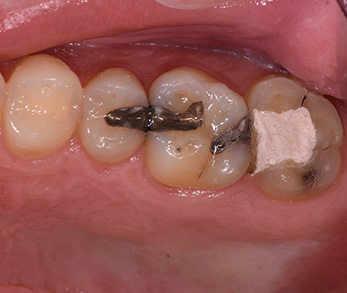

Ceramic Onlay and Crown

Before

After